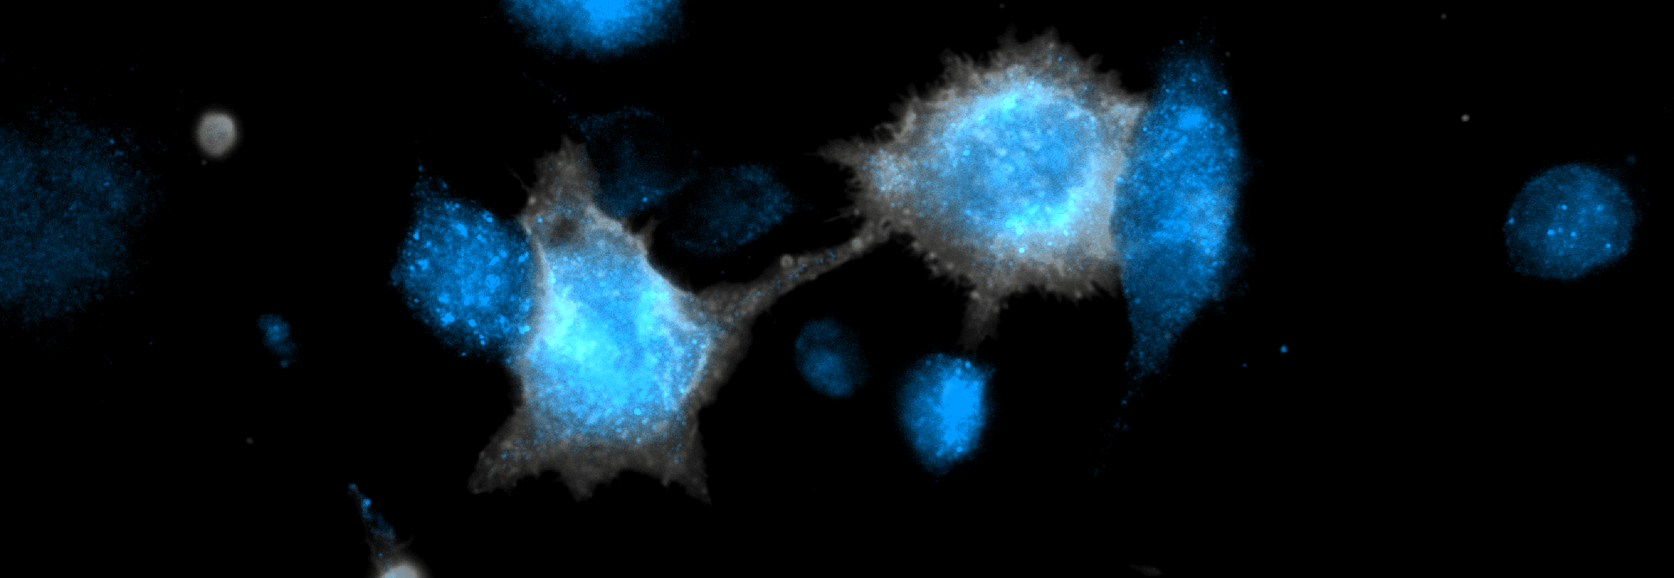

One novel target antigen appears to be  localized at the leading and trailing edge, the “foot” of a migrating tumor cell (figure). A monospecific antibody targeting this tumor antigen significantly inhibits tumor growth in animal studies. This antibody is engineered as not to support an immune cell response, thus binding the target sTA appears to suffice for tumor growth inhibition. Targeting the leading or trailing edge of a tumor cell can focus treatment to tumor cells that are actively involved in invasion and metastasis, the most lethal aspects of cancer.

A tumor antigen, with a predominantly diffuse punctate pattern on non-adherent tumor cells (left panel), concentrates at cell edges with spreading (center panel; arrows).   The tumor antigen distribution is consistent with the leading and trailing edge, or” foot”  of tumor cells with a migratory morphology (right panel; arrows).

Left and center panel; a non-adherent and adherent colon tumor cell line was stained with a Synergy IMT antibody specific for the tumor antigen(green). Red stain (propidium iodide) indicates a large non-viable cell.

Right panel; a breast tumor cell line, was stained with a cell permeant mitochondrial stain (red), PFA fixed and stained with Synergy IMT antibody specific for a novel tumor antigen (green).